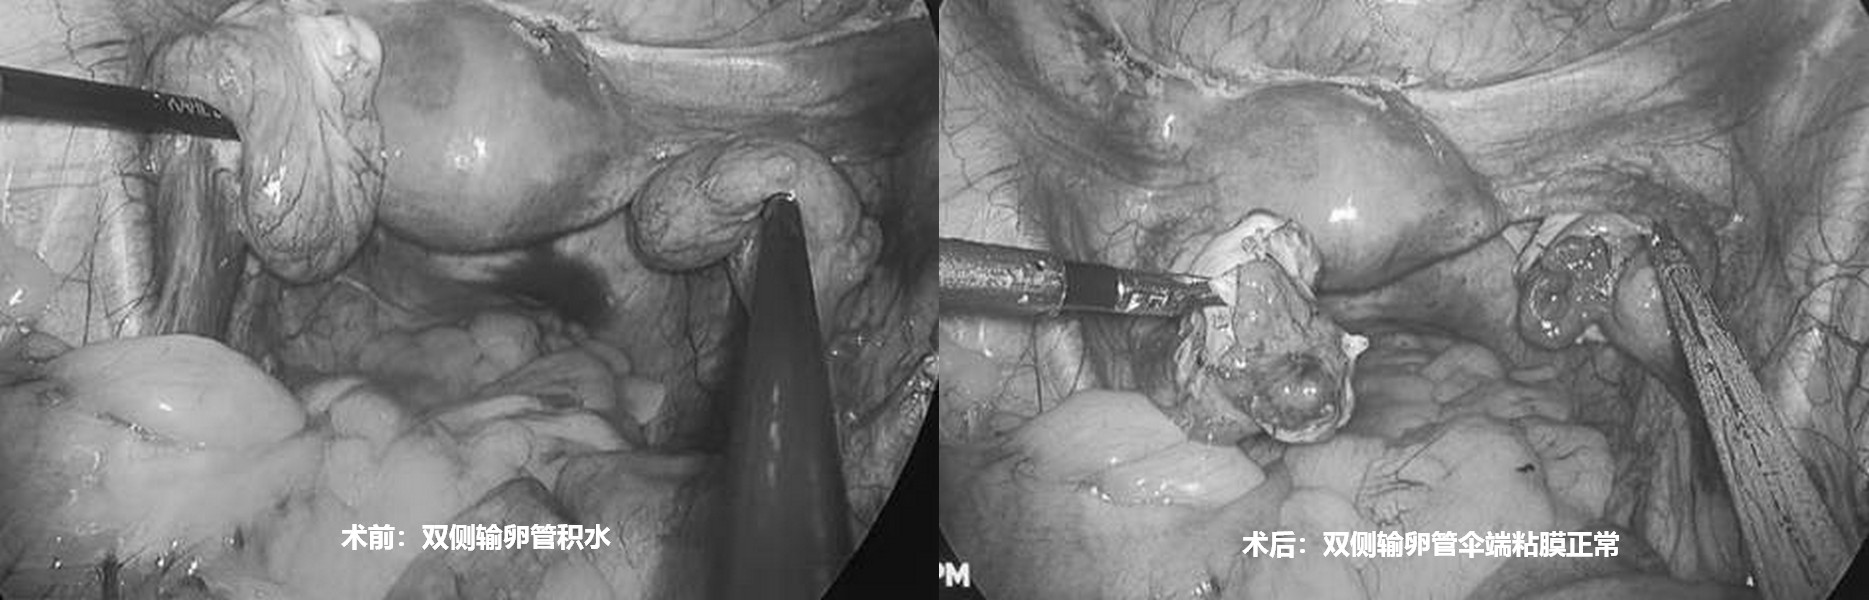

输卵管积水,想怀孕的最好方式是什么?